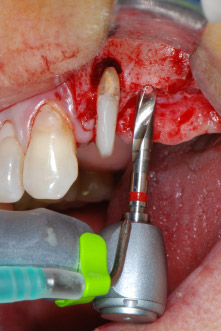

However, we maintained our initial plan to retain both teeth as temporary bridge abutments during the six-months osseointegration period of the implants. At reentry, the situation would have to be reassessed. First, in an attempt to manage the endo-perio problem, the remaining root surface was carefully debrided with piezoelectric equipment (Piezomed, W&H, used with the spatula-shaped insert S1, originally designed for erosion of the lateral sinus wall) (Fig. 4).

Then the apex was abraded with the same instrument to remove residual infected apical tissue and to reduce possible accessory root-canal ramifications (apicoectomy) (Fig. 5). A retrograde filling was not necessary because the orthograde filling had just been revised.

Fig. 4: To preserve the tooth as a temporary abutment, the periodontium was debrided with piezoelectric equipment …

buccal apex of tooth 24

Fig 5: ... and the buccal apex of tooth 24 was abraded with the same instrument (apicoectomy).

Due to its precise and gentle action, both the periodontal debridement and the apicoectomy at site 24 were carried out with a piezoelectric unit (Fig. 19). To avoid the risk of losing the tooth, thorough cleaning was necessary, but without exerting too much pressure. The device was also useful for debriding the bone at the surgical site, which works very well given the specific cavitation effect and cutting characteristics of the technology.